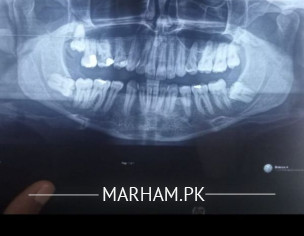

Asking For Self, Male 30, Lahore

mujhe 4 years pehle braces lge ab kafi arse se retainer use ni kr raha shuro me kuch saal plastic retainer use krta rha..

agar ab use na kru tou mazeed relapse k chances tou ni hote

ar wisdom tooth and upper wala jo mukammal nikla ni wo nikalwana zaruri tou ni wase filhaal maxla koi ni un me ??

impacted must removed

extract it because in old age immunity is less and it will be difficult for you later better to remove it now

Impacted wisdoms should be extracted. Also get your dental checkup for further diagnosis.

impacted teeth nikalwalo....aur retainer after 4yrs zaroorat nahi.

Get ur impacted teeth removed before it troubles u

Get the impacted teeth removed, no need for retainers at this time.